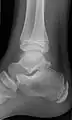

Ankle

Accessory bones at the ankle mainly include:

- Os subtibiale, with a prevalence of approximately 1%.[14] It is a secondary ossification center of the distal tibia that appears during the first year of life, and which in most people fuses with the shaft at approximately 15 years in females and approximately 17 years in males.[14]

- Os subfibulare, with a prevalence of approximately 0.2%.[15]

Os trigonum (further described below) may also be seen on an ankle X-ray.

Os trigonum

The os trigonum or accessory talus represents a failure of fusion of the lateral tubercle of the posterior process of the talus bone. Is estimated to be present in 7–25% of adults.[17] It can be mistaken for an avulsion fracture of lateral tubercle of talus (Shepherd fracture) or a fracture of the Stieda process. In most cases, Os Trigonum will go unnoticed, but with some ankle injuries it can get trapped between the heel and ankle bones which irritates the surrounding structures, leading to Os Trigonum Syndrome.[21]